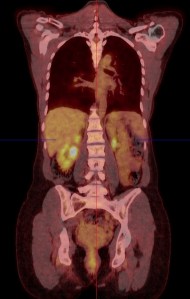

This advanced nuclear imaging technique combines positron emission tomography (PET) and computed tomography (CT) into one machine. A PET/CT scan reveals information about both the structure and function of cells and tissues in the body during a single imaging session.

The last few years have seen unprecedented advances in medical imaging techniques, allowing doctors an extraordinary view into the human body and the opportunity to fine-tune treatment.  PET-CT is well established internationally as the ‘Gold Standard’ for the assessment of the extent of cancer spread in the body as well as the assessment of cancer treatment.